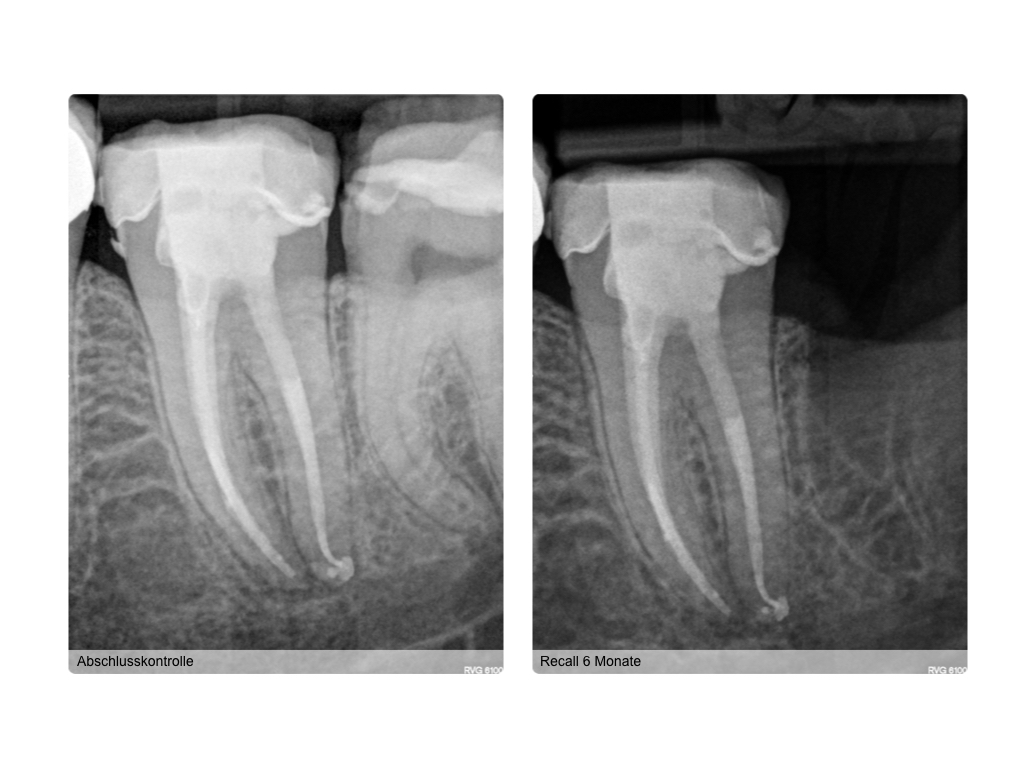

WS_Fallvorstellung15_12_12.008 Veröffentlicht 15. Dezember 2015 am 1024 × 768 in 2015 Fallvorstellung 2